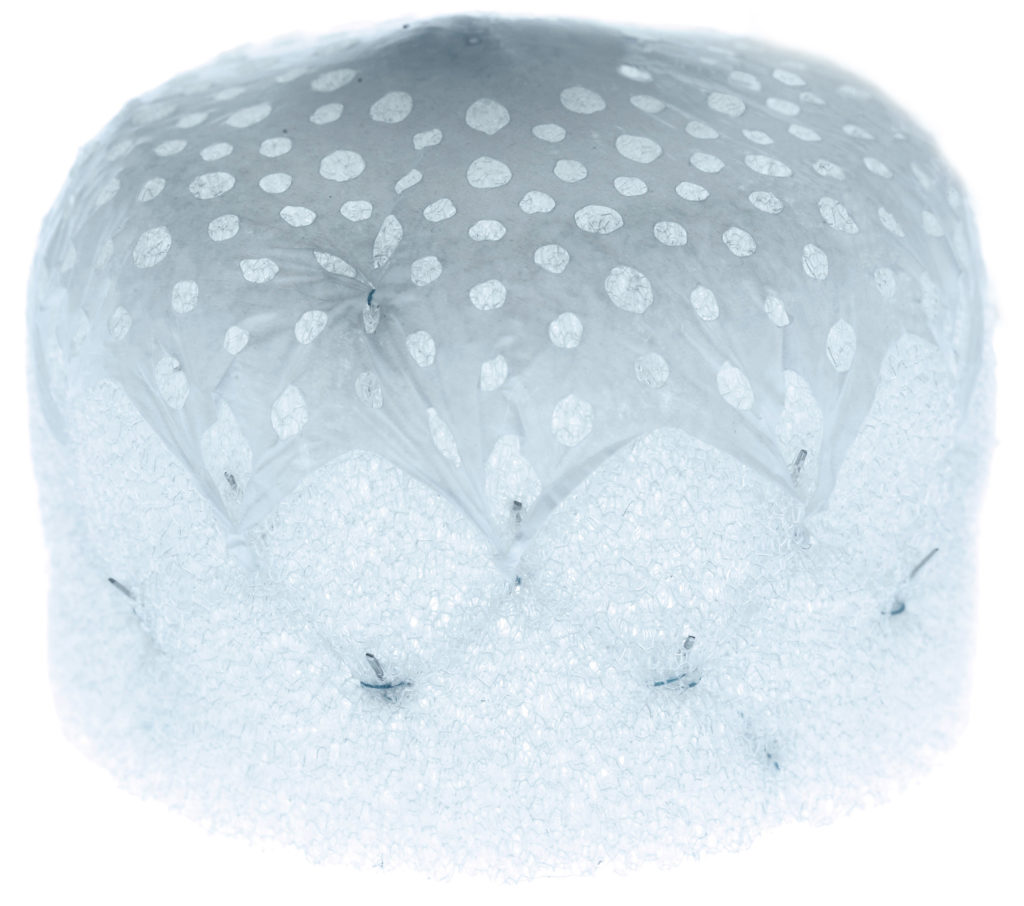

Tiene un esqueleto de nitinol con dos filas de 20 anclajes que se fijan a la pared de la orejuela, con un recubrimiento matricial de espuma en forma de tapón. En la parte superior de este, la expuesta al contacto sanguíneo, lleva un recubrimiento con tejido de politetrafluoroetileno expandido (ePTFE) que evita la trombosis del dispositivo1.

La matriz de espuma permite sellar con mayor eficacia posibles fugas de otros dispositivos, y se adapta a la mayor parte de anatomías de la orejuela con solo dos tamaños. La gran ventaja del recubrimiento de ePTFE es que reduce de manera importante la formación de trombos sobre el dispositivo, sobre todo cuando la anticoagulación o la antiagregación están contraindicadas.